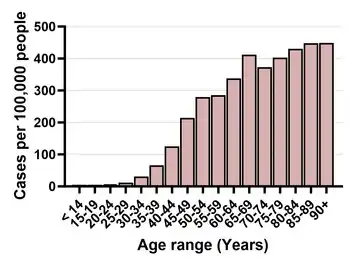

Breast cancer predominantly affects women; less than 1% of those with breast cancer are men.[160] Women can develop breast cancer as early as adolescence, but risk increases with age, and 75% of cases are in women over 50 years old.[160] The risk over a woman's lifetime is approximately 1.5% at age 40, 3% at age 50, and more than 4% risk at age 70.[161]